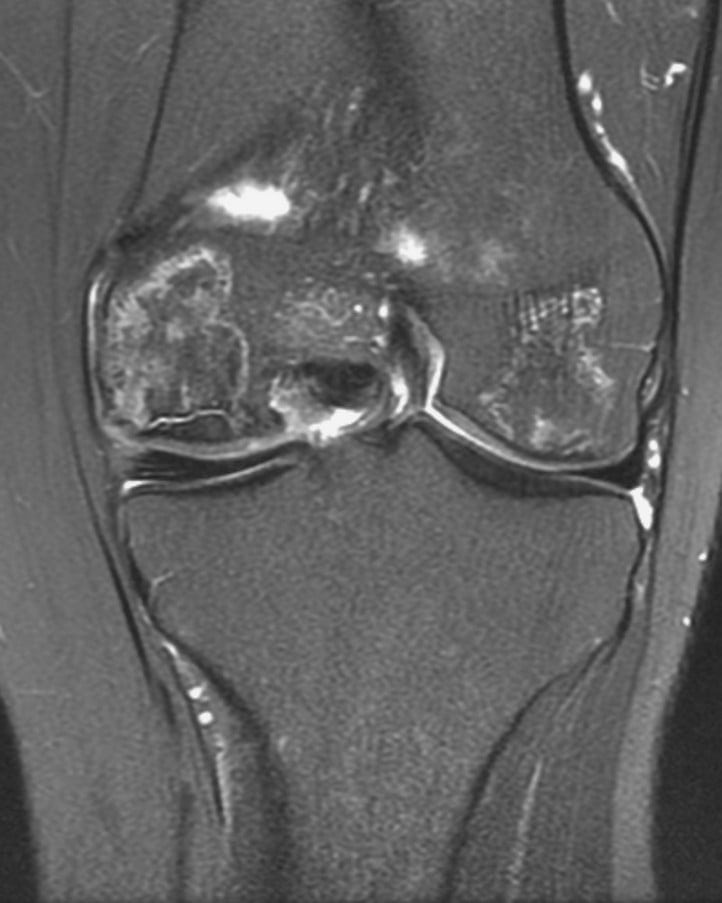

- МРТ. Позволяет выявить даже самые минимальные некротические очаги. Чувствительность магнитно-резонансной томографии на начальных стадиях остеонекроза составляет 90-100%.